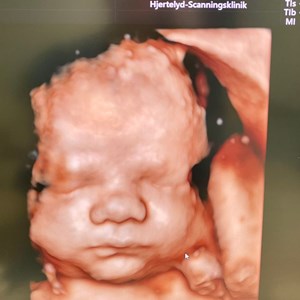

Et spørgsmål jeg tit svarer på : ' Hvornår er det bedst at komme til 3D/4D scanning ?' �...